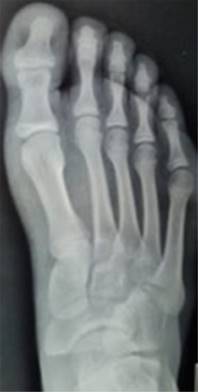

Caso clínico 2. Masculino de 15 años, sufre contusión directa en dorso del pie derecho al jugar fútbol, posteriormente inicia con dolor y marcha antiálgica, motivo por el cual acude a valoración. A la exploración física llama la atención el acortamiento del segundo dedo, con aumento de volumen y edema en dorso de articulación metatarsofalángica del segundo dedo. Se toman radiografías AP y oblicua de pie (Figura 4); evidencian fractura epifisiaria desplazada de la cabeza del segundo metatarsiano.

Figura 4: Radiografías anteroposterior y oblicua del pie de masculino de 15 años. Muestra fractura desplazada de la epífisis del segundo metatarsiano.

Con previo consentimiento de los padres y el paciente, se realiza reducción cerrada bajo anestesia local, se comprueba adecuada reducción con control radiológico (Figura 5). Se coloca zapato postquirúrgico y se inicia marcha a tolerancia. En seguimiento a corto, mediano y largo plazo sin evidencia de complicaciones; se anexan radiografías (Figura 6) a 30 meses de evolución.

Figura 5: Radiografías anteroposterior y oblicua del pie posteriores a reducción cerrada de la fractura. Se observa restitución de la anatomía y longitud.